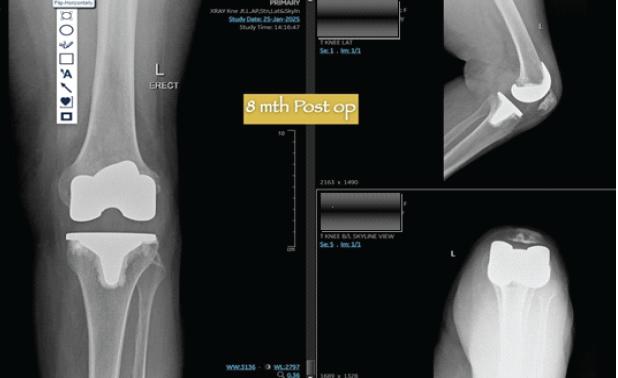

By the 3-month post-operative visit, the patient reported markedly improved subjective knee confidence and achieved unassisted ambulation. At the 6-month mark, she had successfully resumed stair climbing and independent performance of daily activities without difficulty. Validated functional outcome scores demonstrated substantial improvement: the Knee Injury and Osteoarthritis Outcome Score increased from 42 preoperatively to 82, and the Western Ontario and McMaster Universities Osteoarthritis Index decreased significantly from 48 to 18. The dial test remained negative at all assessments. At the latest follow-up of 8 months, the patient had returned to a physically active lifestyle without functional limitations. Radiographic evaluation confirmed maintained implant position and alignment. Clinically, there was no evidence of instability, graft failure, or excessive polyethylene wear. Dynamic assessment confirmed central alignment of the RP insert without rotational subluxation (Fig. 6).

Figure 6: Eight-month follow-up X-rays showing no secondary laxity or alteration in the alignment.